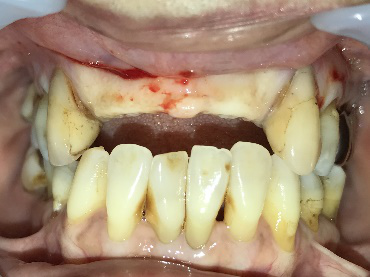

男性Yさん 60代(インプラント)

主訴

上前歯2本の歯根が割れているので、インプラント治療をしてほしい。

治療内容

前歯2本を抜歯し、同時に骨造成をしました。骨ができる期間を約5か月待ち、インプラントを2本埋入しました。

所感

インプラント治療を希望し、函館から車で1時間10分ほどかかる江差町の歯科医院から、紹介されて来院されました。前歯2本は、歯根が破折していました。歯根の割れ方が、小さければ抜歯せず保存できる場合がありますが、この症例は真っ二つに割れていましたので抜歯せざるを得ませんでした。

抜歯前に、抜歯後の治療法について詳しく説明したところ、インプラント治療を希望されました。歯根が破折した状態で、1年以上経過していましたので、歯根の周りの骨が大きく欠損していることがわかりましたので、抜歯と同時に骨造成をすることを計画しました。抜歯と骨造成後、5か月を待ち、X-Guideを使用し、正確にインプラントを埋入しました。

骨造成:¥55,000(税込)

インプラント2本:¥363,000×2本=¥726,000(税込)

合計:¥781,000(税込)

Before

After